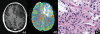

We evaluate the value of MR diffusion tensor imaging (DTI) and dynamic susceptibility-weighted contrast material-enhanced perfusion-weighted imaging (PWI) in preoperative grading of supratentorial nonenhancing gliomas. This institutional review board-approved, Health Insurance Portability and Accountability Act-compliant retrospective study involved 52 patients: 37 with low-grade gliomas (LGGs) and 15 with high-grade gliomas (HGGs). The mean trace apparent diffusion coefficient (ADC), minimal ADC, mean fractional anisotropy (FA), maximal FA, and maximal relative cerebral blood volume (rCBV) ratio of the lesions were measured and compared between LGG and HGG. The efficacy of the above parameters in grading supratentorial nonenhancing gliomas was evaluated. There was no significant difference in rCBV ratio, minimal ADC, and mean ADC between LGG and HGG (p > 0.05). The mean and maximal FA values of LGG were significantly lower than the values of HGG (p < 0.001). The receiver operating characteristic analysis showed that the mean FA with a cutoff value of 0.129 and the maximal FA with a cutoff value of 0.219 could differentiate between LGG and HGG with specificity of 69.2% and 76.9%, respectively, and sensitivity of 93.3% and 100.0%, respectively. The combination of mean FA and maximal FA based on the linear discriminant analysis improved the diagnostic accuracy with specificity of 92.3% and sensitivity of 86.7%. These findings were better than maximal rCBV ratio, mean ADC, and minimum ADC. The mean FA and maximal FA, used individually or combined, may be useful in preoperative grading of supratentorial nonenhancing gliomas.